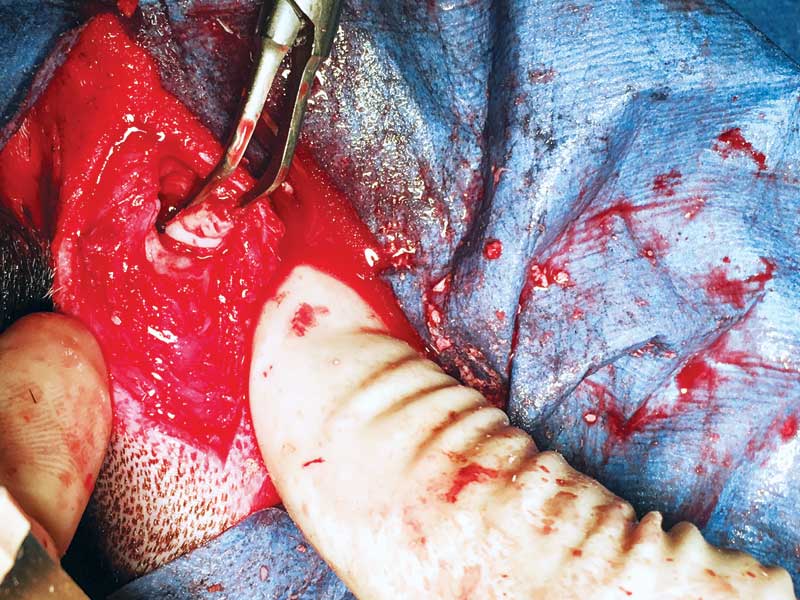

Given the deep location of the tooth, the patient was placed in dorsal recumbency and the area on his lower-right mandible below tooth #408 was surgically prepared. A hypodermic needle was placed and further radiographs were performed to help determine the exact location of the impacted premolar within the mandible (Figure 3). A surgical incision was created and the underlying mandibular bone was exposed (Figure 4). Using a #8 round bur and copious lavage with sterile saline, the mandibular bone was slowly removed until tooth structure was visualized (Figures 5 and 6).

With the location of the tooth structure determined, a winged elevator was used to begin elevation (Figure 7). Even with an impacted tooth, the periodontal ligament can be intact and produce as strong a hold as any tooth that erupts normally. With proper elevation technique using a winged elevator and exercising patience, the impacted tooth was elevated and removed completely (Figures 8 and 9). The entire alveolus in which the tooth was embedded was debrided to remove potential remnants of a cyst lining the alveolus. It is extremely important to debride the alveolus well, since any retained cyst material can continue to progress and destroy bone. Post-extraction radiographs confirmed complete removal. A follow-up dental radiograph three months later showed adequate healing and supportive bone growth.